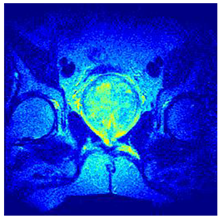

Table 5 presents the segmentation of the MRIs using EO for a qualitative inspection. From Figure 5, it is clear that two lumps in the prostate have been highlighted by the thresholding process. Prostatic MRIs present noisy conditions, which makes it difficult to visualize the thresholding with the naked eye, so in Figure 5 we present the thresholded image as well as the histogram with the values of the thresholds generated by the EO. It can be observed in the histogram that the thresholds present an adequate distribution, even though this particular image has impulsive noise and a simple shape. Our findings indicate that four thresholds are typically sufficient for this application, which corresponds to identifying five different tissue types in the image. A smaller threshold value may result in a lack of sufficient contrast to highlight relevant anatomical structures, such as the prostate capsule. In contrast, a higher number of thresholds may lead to the incorrect differentiation of anatomical regions that should be connected.

Table 5.

Segmentation of transaxial-cut prostate MRI images Using EO and cross-entropy. This table presents the segmentation results of transaxial-cut prostate MRI images using the equilibrium optimizer (EO) and cross-entropy. Each row corresponds to a distinct MRI image, while the columns nt represent the number of thresholds applied during segmentation. The results illustrate the performance of the EO algorithm across different threshold levels for each image.